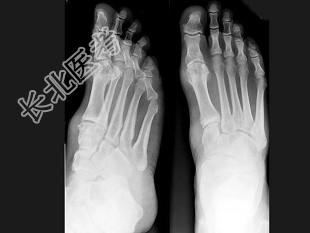

- 单项选择题男,47岁, 关节炎病史20年,结合图像, 最可能的诊断是 ( )

A、类风湿关节炎

B、痛风

C、骨关节结核

D、牛皮癣性关节炎

E、Reiter综合征